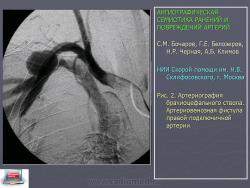

Травматические артериальные аневризмы образуются в результате ранения или закрытой травмы сосудистой стенки, представляют собой организовавшуюся пульсирующую гематому. Клинически такие образования проявляются припухлостью, пульсацией и шумом, что нередко сопровождается болевым синдромом и ишемическими расстройствами. Наличие турбулентного кровотока в полости аневризмы является фактором риска тромбоэмболических осложнений. При артериовенозных соустьях, которые нередко сопутствуют ложным аневризмам, происходит контрастирование вен в раннюю артериальную фазу (рис. 2).

Рис. 2. Артериография брахиоцефального ствола. Артериовенозная фистула правой подключичной артерии

Выраженный артериовенозный сброс и объемная перегрузка правых полостей сердца могут стать причиной появления симптомов сердечной недостаточности [6]. Артериовенозные соустья обнаружены у 7,2% обследованных пациентов. Отслойка интимы ангиографически выявляется по наличию дополнительной структуры в просвете сосуда (рис. 3).